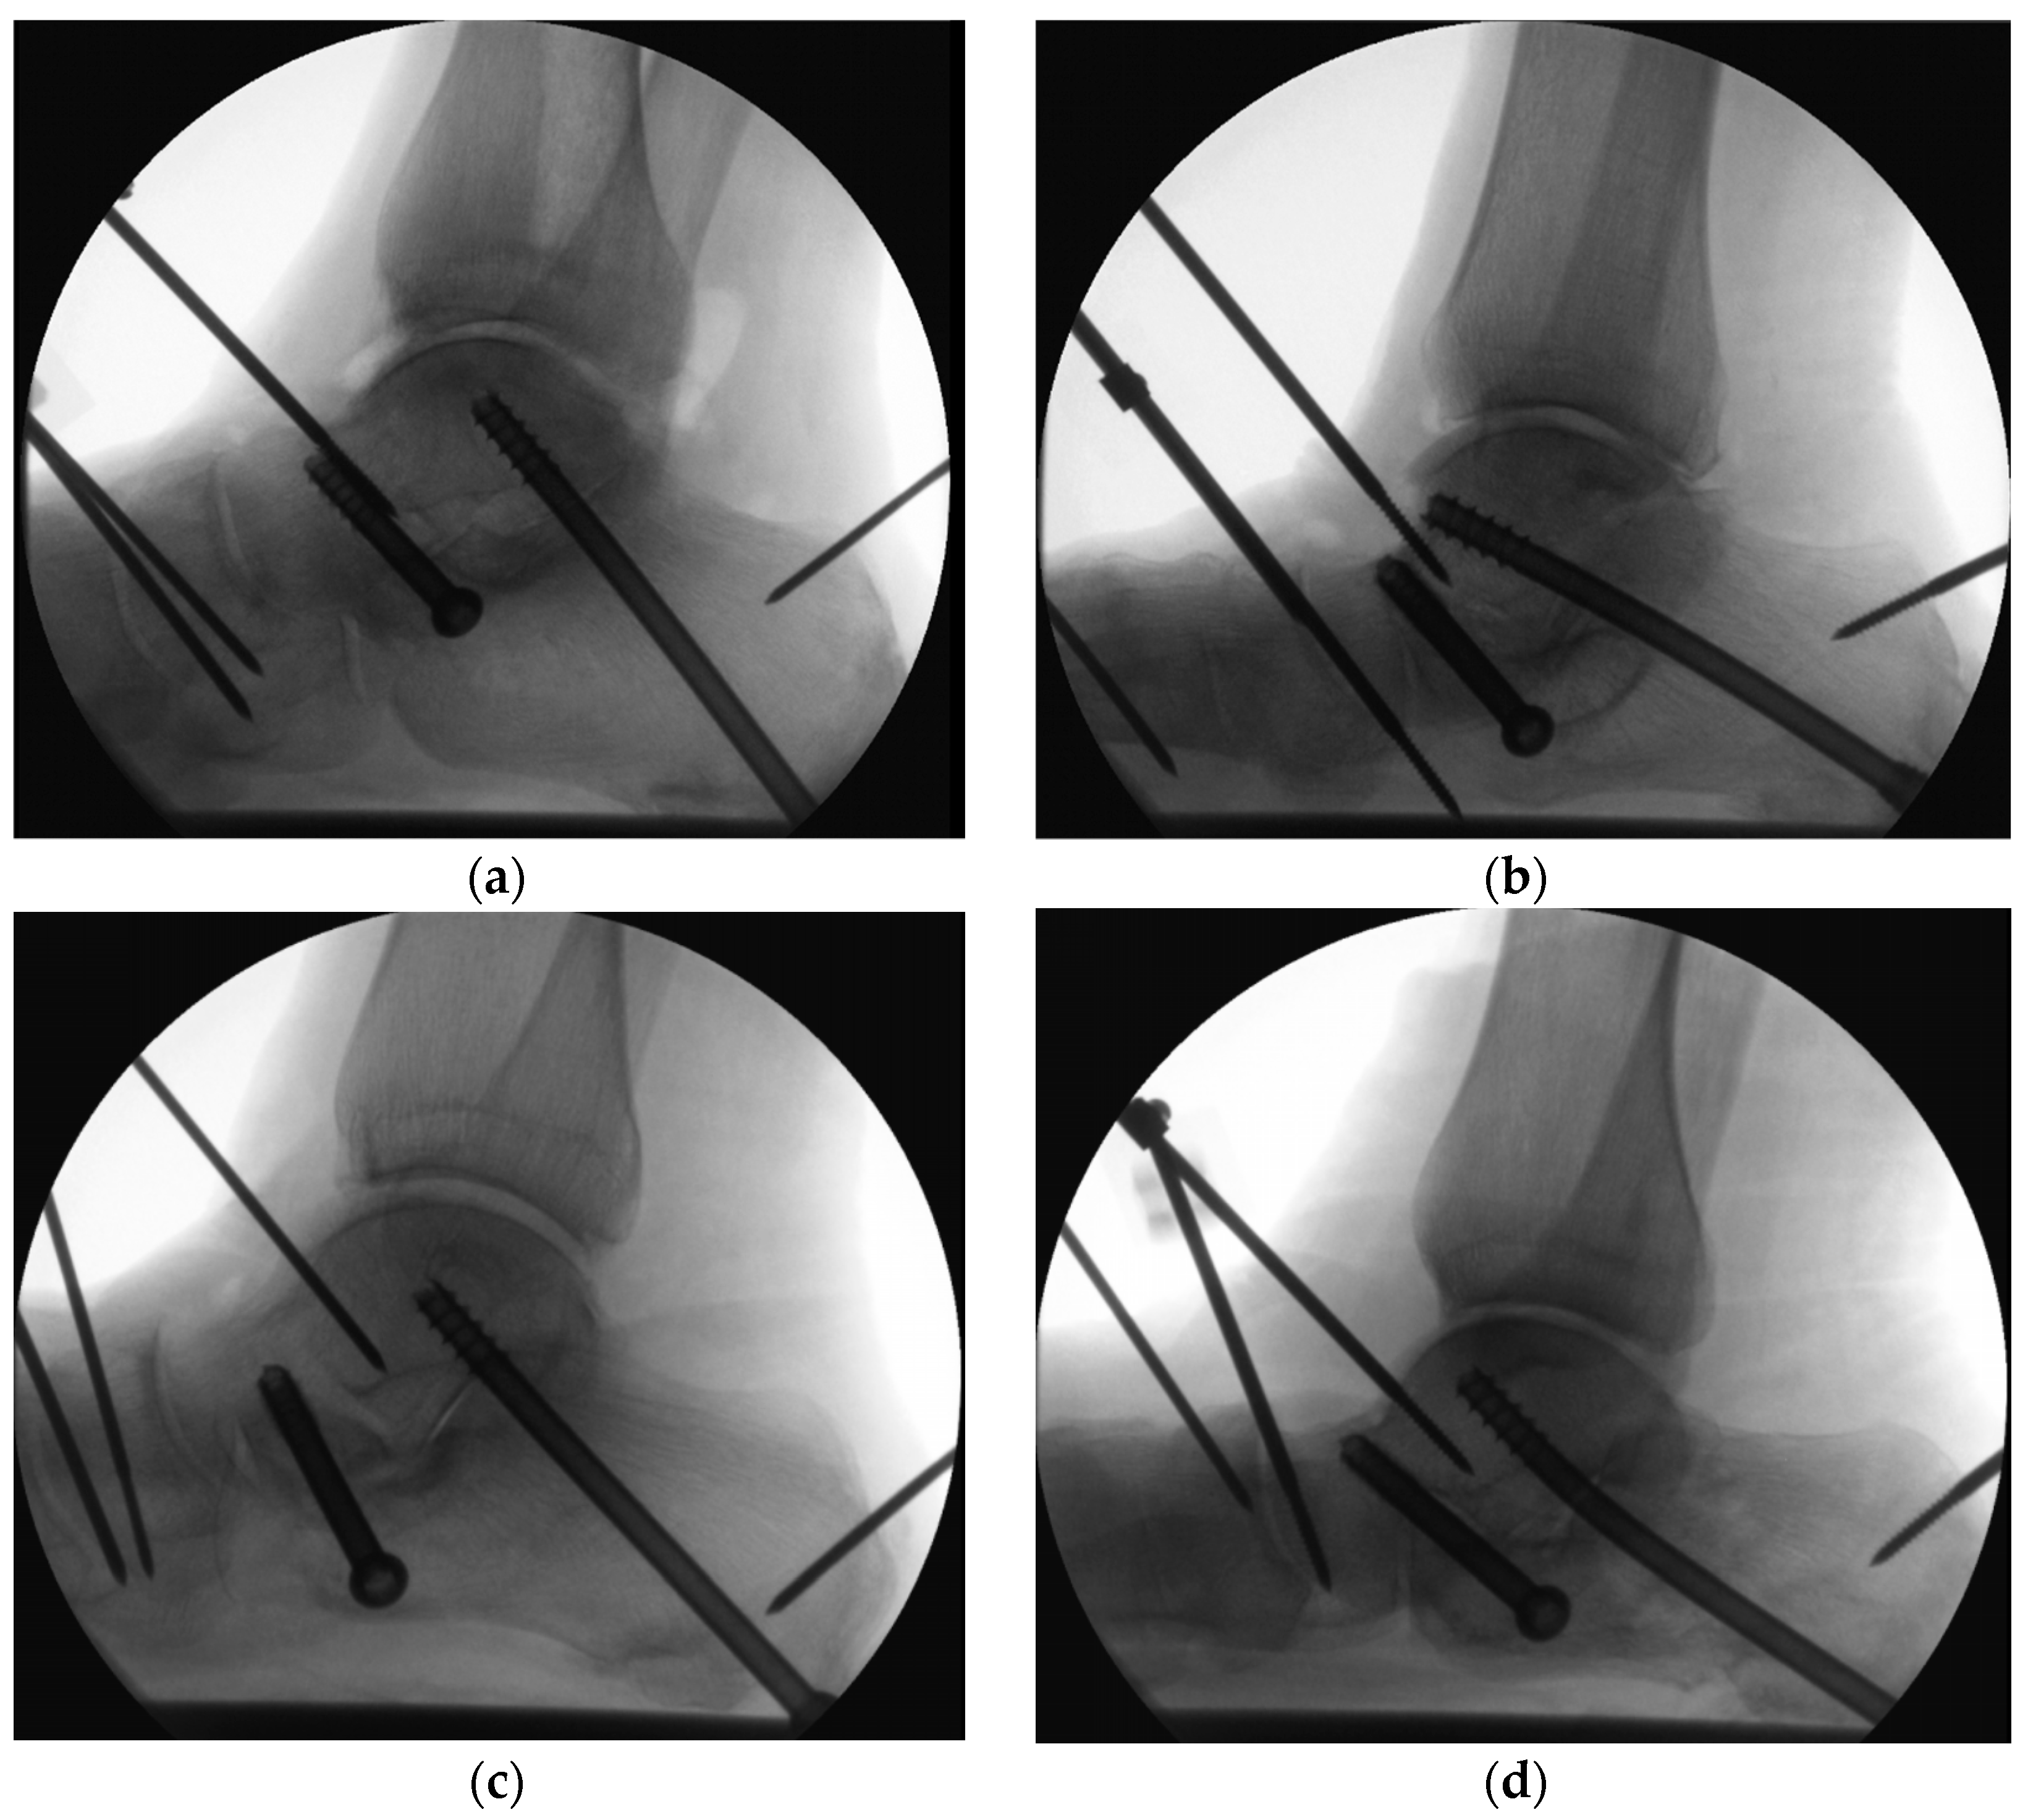

2. Materials and Methods

2.1. Specimens and Preparation

2.2. Biomechanical Testing